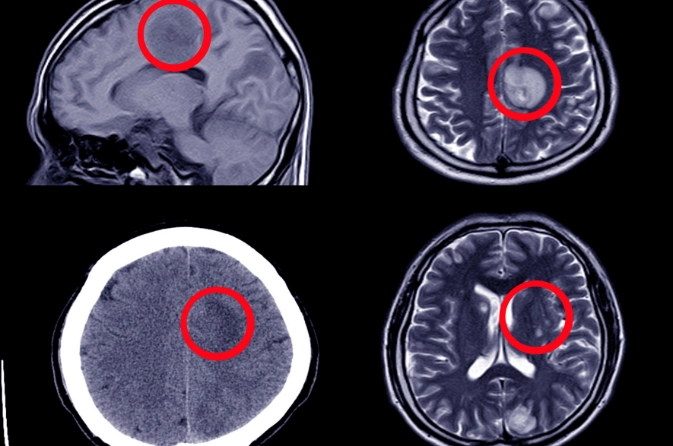

Diagnosis for the Subarachnoid Hemorrhage

Diagnosis of subarachnoid hemorrhage begins with a detailed clinical evaluation and neurological examination. A non-contrast CT scan of the brain is the primary test to detect bleeding. If CT findings are unclear, a lumbar puncture may be performed. Additional tests such as CT angiography or cerebral angiography help identify the source of bleeding, such as a ruptured aneurysm.